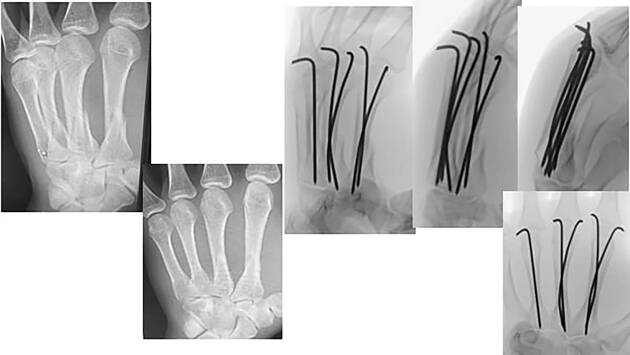

Как оказалось, из-за силы удара кисть переразогнулась, и парень получил перелом оснований трех пястных костей сразу. Поскольку переломы были со смещением, подростка прооперировали. Ему провели репозицию пястных костей и остеосинтез — вставили в поврежденные кости металлические спицы по специальной методике с изгибанием. Кроме того, из-за сложности случая спицы также пришлось направлять вручную.

Из-за необычного рентгеновского снимка, на котором кажется, что кисть пациента наполовину состоит из металла, врачи прозвали его «Росомахой» в честь супергероя из комиксов Marvel. По сюжету у Росомахи в кистях скрыто по три металлических лезвия, которые могут выдвигаться.

Подростку наложили гипс. Через четыре недели его ждет повторная операция, в ходе которой хирурги удалят металлические спицы.